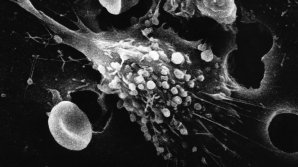

Тэги: метод Ученые: Популярный метод борьбы со старением не действует Молекулы-самоубийцы могут защитить нас от рака 1 ABCDEFGHIJKLMNOPQRSTUVWXYZ IMPORTANTE ALTELE